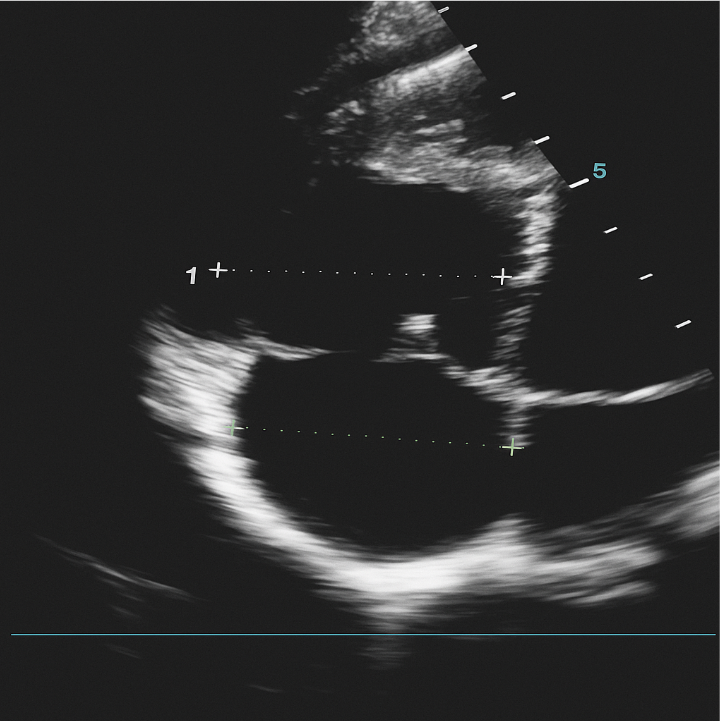

His basic laboratory tests included white blood cell (WBC) 7.1k/mcL (65.3% neutrophil, 26.5%lymphocyte), hemoglobin 18g/dL (hematocrit 51.7%), platelet count 380k/mcL; creatinine 0.67mg/dl, urea 29mg/dl, sodium 140mmol/L, potassium 3.79mmol/L, chloride 98mmol/L, ionized calcium 1.19mmol/L. His echocardiography (Figure 1) showed dilated RV (basal diameter 49mm) and right atrium (RA minor dimension 47mm), dilated main pulmonary artery (MPA) (26mm), tricuspid regurgitation velocity (TRV) 3.6m/sec; concluded as severe pulmonary hypertension (right ventricular systolic pressure/pulmonary artery systolic pressure (RVSP/PASP) 65mmHg), RV systolic dysfunction (TAPSE 14mm, RV fractional area change (FAC) 17%) but normal left ventricular function (LVEF 65%).

Figure 1: 4-chamber view echocardiography with right-sided chamber dilatation